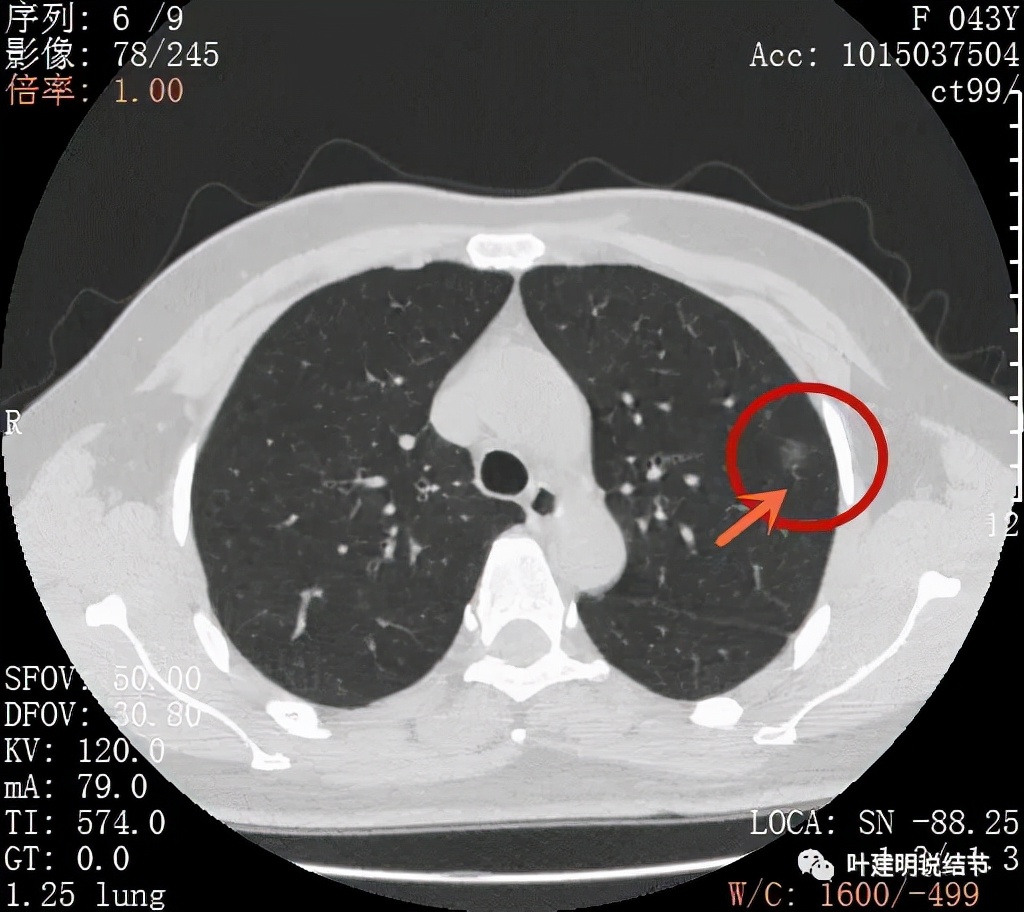

病灶密度较低,膨胀性略,瘤肺边界在靶扫描上还是显得有些清晰的

病灶瘤肺边界清,密度偏低,有点散,但有微小血管进入(桔色箭头)

病灶整体密度较低,但轮廓较清,内部密度不大均匀,显得杂乱